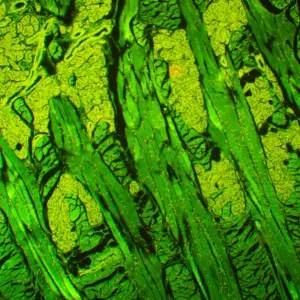

Микроскоп MAGUS Lum 450L – это модель, на которой можно проводить исследования как в светлом поле, так и в свете люминесценции, а при доукомплектовании микроскопа дополнительными компонентами станут доступны и исследования по темному полю, фазовому контрасту или в поляризованном свете. При исследованиях в свете люминесценции MAGUS Lum 450L освещает препарат синим или зеленым цветом – объекты, соответственно, производят зелено-желтый или красный свет. Люминесцентные микроскопы применяются в медицинских экспертизах, криминалистических или фармакологических исследованиях, в работе ветеринарного контроля и санэпиднадзора. Эта модель оснащена системой «умного» освещения, подстраивающей интенсивность света под характеристики объектива, и ЖК-экраном, на котором можно контролировать параметры работы.

- Для работы в свете люминесценции препарат освещается синим или зеленым светом и производит желто-зеленый или красный